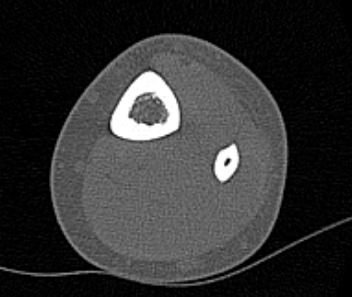

Во время исследования рентгеновская трубка томографа вращается вокруг исследуемой области и производит множество послойных снимков с шагом от 0,5 мм. Полученные снимки поперечного сечения с помощью компьютерной программы могут быть преобразованы в 3D-изображения исследуемого органа. Это позволяет выявлять различные патологические процессы на начальных стадиях и назначать своевременное лечение.

За счет быстроты, доступности и неинвазивности (то есть исследование не требует вмешательства в организм) метод КТ особенно востребован в ортопедии и травматологии. Мультиспиральная КТ лучше всего визуализирует плотные ткани, такие как кости и хрящи. Поэтому, в первую очередь, применяется для диагностики травм суставов (вывихов, подвывихов, переломов).

В отличие от обычного рентгена, при котором изображения костных структур накладываются друг на друга, что затрудняет диагностику, компьютерная томография дает возможность увидеть объемную модель сустава, наглядно оценить пространственное соотношение внутрисуставных структур, суставных поверхностей, расположение костных отломков при переломах и травмах. Это особенно важно в ходе подготовки к оперативному вмешательству и в послеоперационном периоде для оценки успешности проведенной операции.